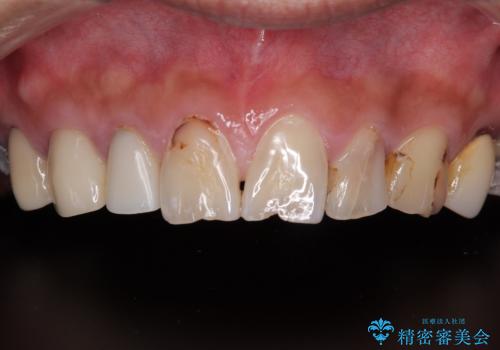

- 患者様は「前歯の見た目をきれいにしたい」というご希望で来院されました。

拝見すると、上顎前歯部にはCR充填(レジン修復)が繰り返し行われており、つぎはぎ状になっていました。そのため、

色調が不自然

形態にばらつきがある

笑ったときに治療跡が目立つ

といった審美的なお悩みが認められました。

また、右上側切歯は根管治療が必要な状態でした。

右上側切歯に対して根管治療を行い、その後右上側切歯から左上犬歯まで計5本をオールセラミッククラウンで補綴する治療計画をご提案しました。